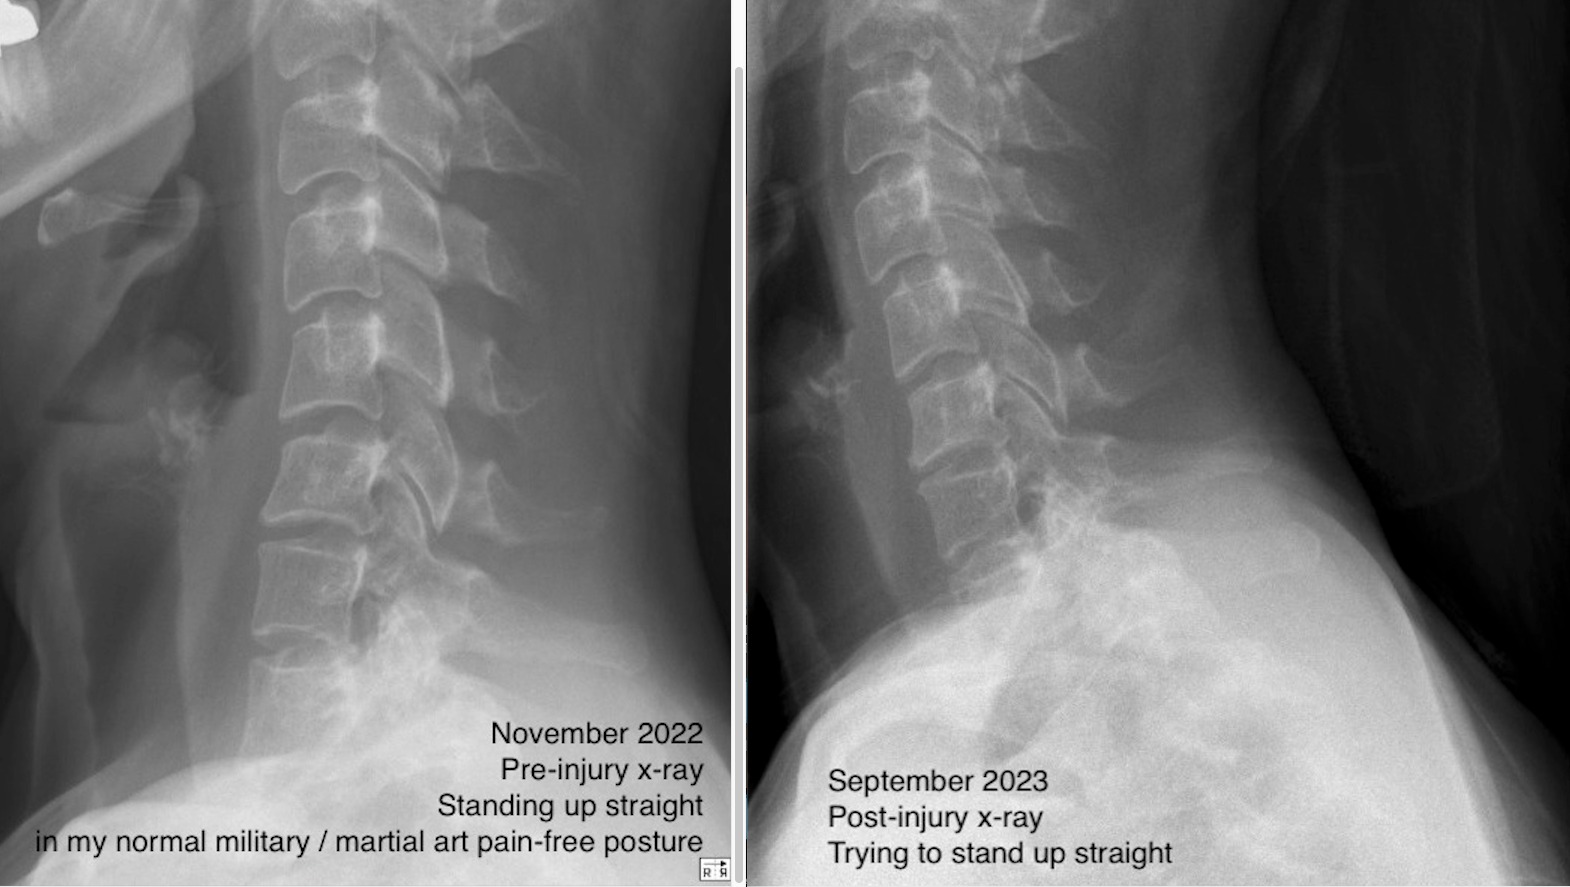

X-rays from (healthy uninjured) 2022 compared to (injured) 2023 show the significant change in alignment which alters function. The MRI reveals the injury left me with three herniated cervical discs.

I have torn ligaments, dislocated collarbone, shoulder, jaw and ribs. My spine is 'stacked', my torso compressed. The muscles in my neck, back and chest seemed to have lost most of their energy or sense of purpose. In all of this, I experience partial numbness in my lips, face, neck, hands and feet, great muscle weakness and ataxia. I feel my cervical vertebrae against my throat where it shouldn’t be.